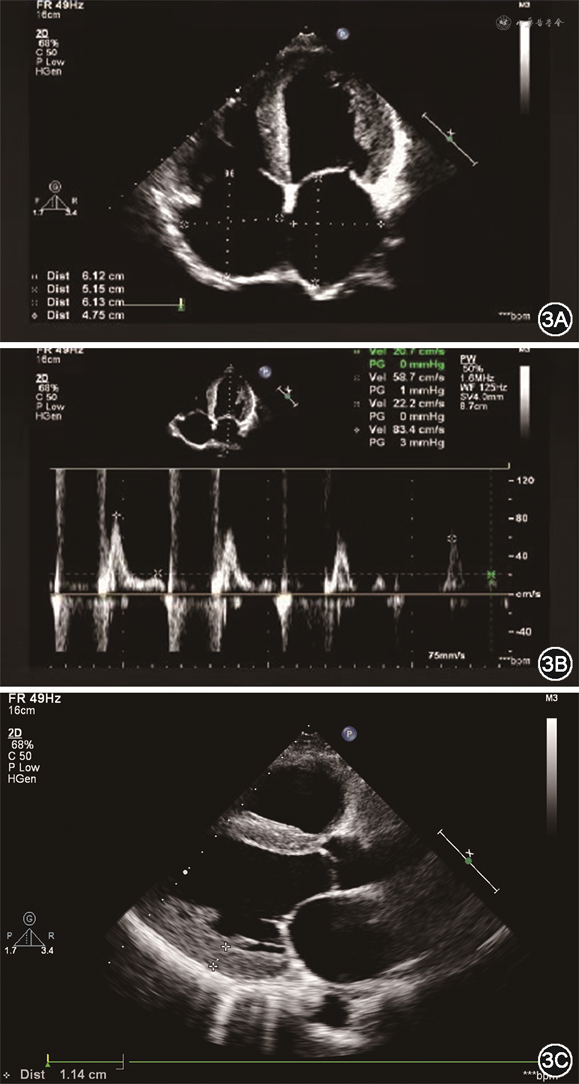

患者男性,41岁,主因“劳力性气短1月,加重1周”于2019年7月17日入院。2019年6月初活动后出现气短,不伴胸闷、胸痛、咽喉部紧缩感及肩背部放射痛,稍事休息可缓解,未诊治。7月10日起气短加重,劳动耐量较前下降,稍活动即感气短,平卧位时亦有气短发作,坐起后可缓解,不伴尿量减少、腹胀及双下肢水肿,为明确诊治来诊。既往史:否认高血压、糖尿病史。2019年4月15日因发热、咳嗽,最高体温为38.4 ℃,于外院行胸部CT示右肺中叶及左肺下叶炎性病灶,部分纤维化,少量心包积液,予抗感染、止咳等治疗后发热、咳嗽缓解。5月10日因左侧头疼伴左半身麻木、呃逆、呕吐行头颅磁共振成像(magnetic resonance imaging,MRI)检查提示急性脑梗死,经改善脑循环、脑保护、稳斑等治疗,无明显后遗症。个人史:吸烟史20年,平均20支/日。入院查体:神志清楚,半卧位,血压100/60 mmHg(1 mmHg=0.133 kPa),颈静脉无怒张,双肺呼吸音清,未闻及干、湿性啰音。心率105次/分,律齐,P2>A2,各瓣膜听诊区未闻及病理性杂音,移动性浊音阴性,双下肢无水肿。心电图:心率96次/分,V1-V4导联R波递增不良(图1)。胸片:双肺纹理增重,心界扩大(图2)。血常规、肝肾功能、电解质、凝血正常范围。心肌肌钙蛋白I(cardiac troponin I,cTnI)0.06 ng/mL,N末端B型利钠肽前体(N terminal-pro B type natriuretic peptide,NT-proBNP)6645.9 pg/mL。动脉血气分析:酸碱度(pH)7.409,二氧化碳分压(PCO2)33.5 mmHg,氧分压(PO2)70.4 mmHg。冠状动脉造影示:未见斑块及有意义狭窄。超声心动图示(图3):双心房增大,左心室、右心室稍大,左心室壁稍增厚,右心室壁厚约3.5 mm。二尖瓣舒张期血流频谱呈双峰,E/A>2。估测肺动脉收缩压约为37 mmHg,左心室射血分数32%,缩短分数15%,左心室舒张末期容积128mL,左心室收缩末期容积87mL,每搏量41mL,心输出量3.18L/min。心脏MRI检查示(图4):双心房增大,左心室壁稍厚,心肌首过灌注示未见明显异常灌注减低或缺损,延迟扫描示室间隔中段可见壁间线状强化,左心室下壁、侧壁及右心室游离壁可见广泛心内膜下强化。心内膜活检及心肌免疫组化示(图5):心肌细胞轻度肥大,心肌细胞间可见淀粉样物质沉积,刚果红染色(+),轻链λ(+),甲状腺素转运蛋白(transthyretin,TTR)(+)。血清免疫球蛋白测定示血清游离轻链(serum free light chain,sFLC)κ 7.67 mg/mL,λ 97.5 mg/mL↑,λ/κ比值(12.7)明显升高。尿本周蛋白:轻链κ 6.63 mg/L,轻链λ 3.66 mg/L。骨髓象及活检(图6):间质内浆细胞散在或灶性浸润(CD138+,κ-,λ+,VS38c+,MUC1散在+,约占15%),局灶可疑有淀粉样物质沉积(刚果红染色弱阳性)。骨髓流式:CD38+CD138+CD27+,轻链λ限制性表达。全身低剂量CT平扫示:颅骨、肩胛骨、肱骨、肋骨、颈、胸椎椎体、骶骨、髂骨、股骨等部位骨皮质变薄,骨小梁稀疏。据上述结果最后确诊为“多发性骨髓瘤、限制型心肌病(心肌淀粉样变)、心功能Ⅳ级(NYHA分级)”。入院后予口服螺内酯20 mg,1次/d,呋塞米10 mg,1次/d,贝前列素钠40 μg,3次/d,比索洛尔片5 mg,1次/d,辅酶Q10,10 mg,3次/d及重组人B型利钠肽治疗,气短症状明显缓解,夜间平卧位休息。后行BD方案(硼替佐米、地塞米松)化疗,化疗第3日患者心功能突发恶化,不能平卧,伴腹胀及双下肢浮肿,遂停止化疗,再次予重组人脑利钠肽及利尿治疗后心能明显改善,可耐受日常活动及平卧位,后症状好转后出院。院外患者规律口服贝前列素钠、螺内酯、呋塞米、比索洛尔等药物治疗,但2020年3月15日于院外猝死。

限制型心肌病(RCM)是一种室壁僵硬度升高导致心室舒张功能显著下降为特点的心肌疾病,属混合型心肌病,可分为特发性、家族性或继发于不同的系统性疾病。其诊断依据为:心室限制性舒张功能障碍,伴一侧或双侧心室舒张末期容积或收缩末期容积正常或缩小,室壁厚度正常,并除外缺血性心肌病、心脏瓣膜病、心包疾病和先天性心脏疾病[1]。临床表现为左和(或)右心衰竭,如乏力、气短、体力活动受限、水肿、晕厥、栓塞或各种心律失常等。心电图可有巨大P波、传导阻滞、低电压或R波递增不良表现。超声心动图是最重要的检查手段之一,二维超声心动图其特点为心房增大,心室正常或缩小,部分患者表现为巨大心房。M型超声表现为室壁偏厚,活动明显减低,舒张期左心室内径变小,容积减小,射血分数及短轴缩短率明显减小。多普勒超声可见二尖瓣、三尖瓣关闭不全,二尖瓣口血流呈限制性充盈障碍表现,E峰高尖,E/A>2,E波减速时间缩短,等容舒张时间缩短等。心脏MRI检查是超声心动图的重要补充,除有助于同缩窄性心包炎鉴别外,结合钆显像可明确RCM的分类[2]。本例患者以劳力性气短、不能平卧就诊,化验NT-proBNP水平升高,符合左心功能不全表现。心电图提示左房增大,伴V1-V4导联R波递增不良,超声心动图提示双心房增大、E/A>2,符合限制型充盈障碍表现。超声心动图提示左心室壁可见点状强回声,结合心脏MRI晚期钆增强,心肌活检刚果红染色阳性可确诊RCM、心肌淀粉样变(cardiac amyloidosis,CA)。